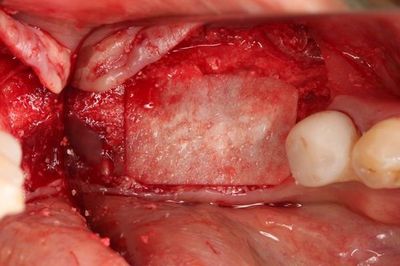

この段階で粘膜剥離して実際の骨の状態を確認します。

この部分は歯根破折と炎症のある歯を抜歯していますので

軟組織が存在し完全な骨性の治癒ではありません。